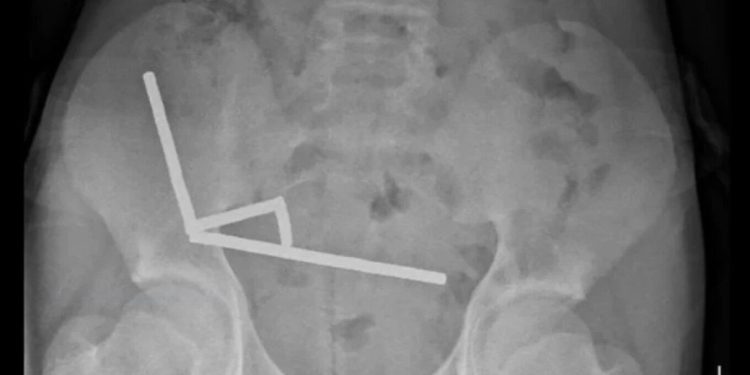

Rrezet X zbuluan se magnetet kishin formuar katër grumbuj të drejta brenda zorrëve. Ato ishin vendosur në pjesë të ndryshme të zorrëve dhe ngjitur së bashku tërësisht nga forcat magnetike. Si pasojë e këtij grumbullimi, kishte ndodhur nekrozë në katër zona të zorrës dhe cekumit, një pjesë e zorrës së trashë. Kirurgët ndërhynë për të hequr indin e vdekur dhe për të rimarrë magnetët.